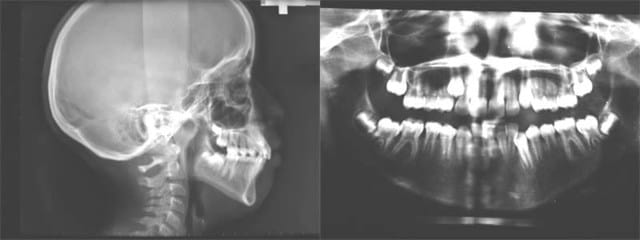

tu as une photo du profil?car sur la radio ca semble tres bipro mais je me mefie

je vais préparer les photos, voici les Rx. éclaircies

Rx - Eugenol